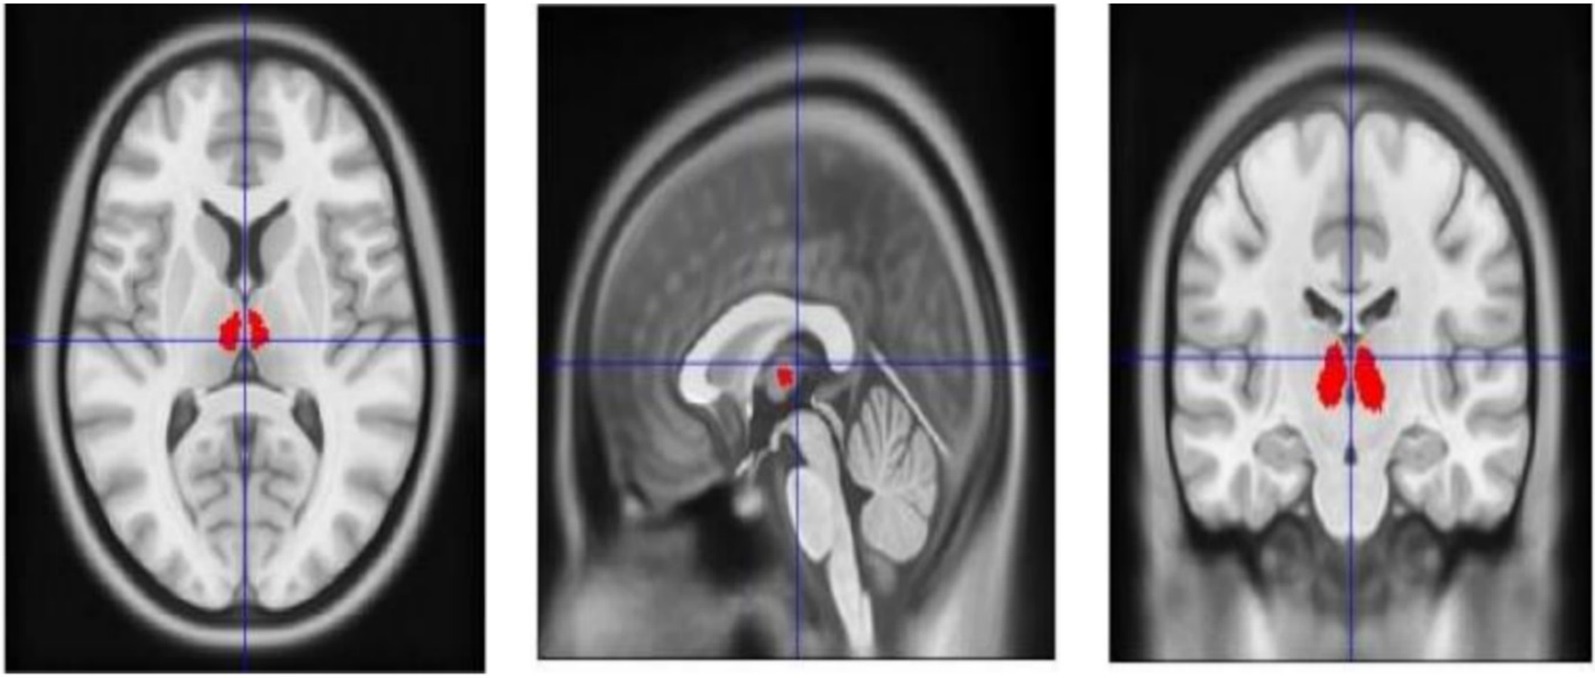

Thalamic mask extraction and normalization: A thalamic mask is extracted from the ALL3 template and then normalized to the individual’s T1-weighted MRI for precise anatomical localization (demonstrative images are provided in Figure 5).

Figure 5

The target of this study is delineated on the MNI template, with the red area specifically indicating the region of interest.

Based on foundational research involving DBS in non-human primates (32), clinical DBS case studies (33), mechanistic insights (34), and accumulated therapeutic experience (19, 20), the stimulation targets for this study are selected from the medial and intralaminar thalamic nuclei group of the ALL3 atlas (35). Specifically, these include the Reuniens nucleus (Thal_RE), the medial magnocellular portion of the mediodorsal nucleus (Thal_MDm), and the lateral portion of the mediodorsal nucleus (Thal_MDl), as well as the intralaminar thalamic nuclei (Thal_IL). The stimulation will target either the left or right side of the thalamus, in accordance with the anatomical references outlined in the ALL3 atlas (35).